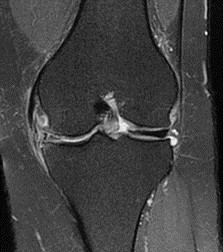

股骨頭骨骺生長板滑脫症的影像診斷,主要以骨盆X光的前後照與蛙腿外展姿勢兩種(圖一&圖二)。影像上可看見骨骺向髖臼後下方移位,並與股骨頸形成夾角。如果X光不明顯,但症狀懷疑的話,可以藉由核磁共振或電腦斷層觀察是否有其他骨骼結構異常的問題,來增加診斷的準確度。

- 核磁共振:非侵入性影像中最精準且敏感的檢查,可以看到半月板有無撕裂造成水腫或是受傷的殘塊。若是桶柄狀撕裂(bucket handle tear)可能會看到double PCL sign或 double anterior horn sign。另外也可能發現半月板撕裂造成的半月板囊腫。